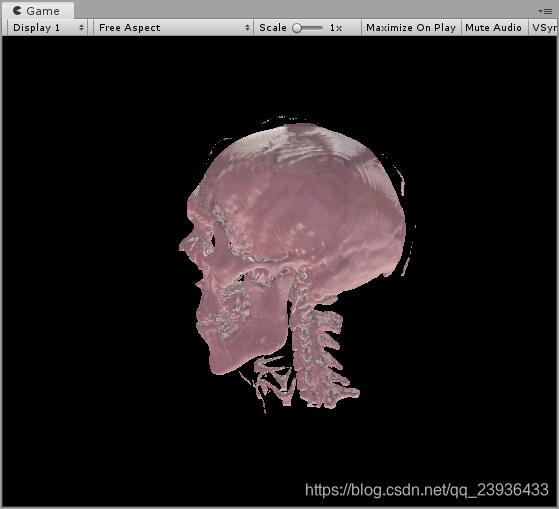

既然我们已经得到了空间中每一个点的密度值,那么我们就可以根据Gradient的方法去计算表面法线了,简单来说就是比较周围的密度值大小,例如在x轴上,如果左侧的减右侧的值大于0,那么该点的法线的x轴向就应该是偏向右侧。我们可以根据以下算法得到法线:

我们既然得到了Object Space的法线,我们就可以根据法线来计算光照了,例如我们可以用一个简单的Blinn-Phong模型来照亮我们的物体,效果如下:

我们也可以用更复杂的光照模型去实现更加好的效果,但是这里我决定用一下MatCap的方法,这是一种非常简单高效的着色方法,可以实现非常有趣的材质效果(ZBrush的视窗材质就是典型的MatCap着色),效果如下: